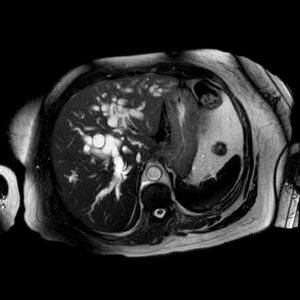

dilatacion de conductos biliares rmn ax

Dilatación de conductos biliares